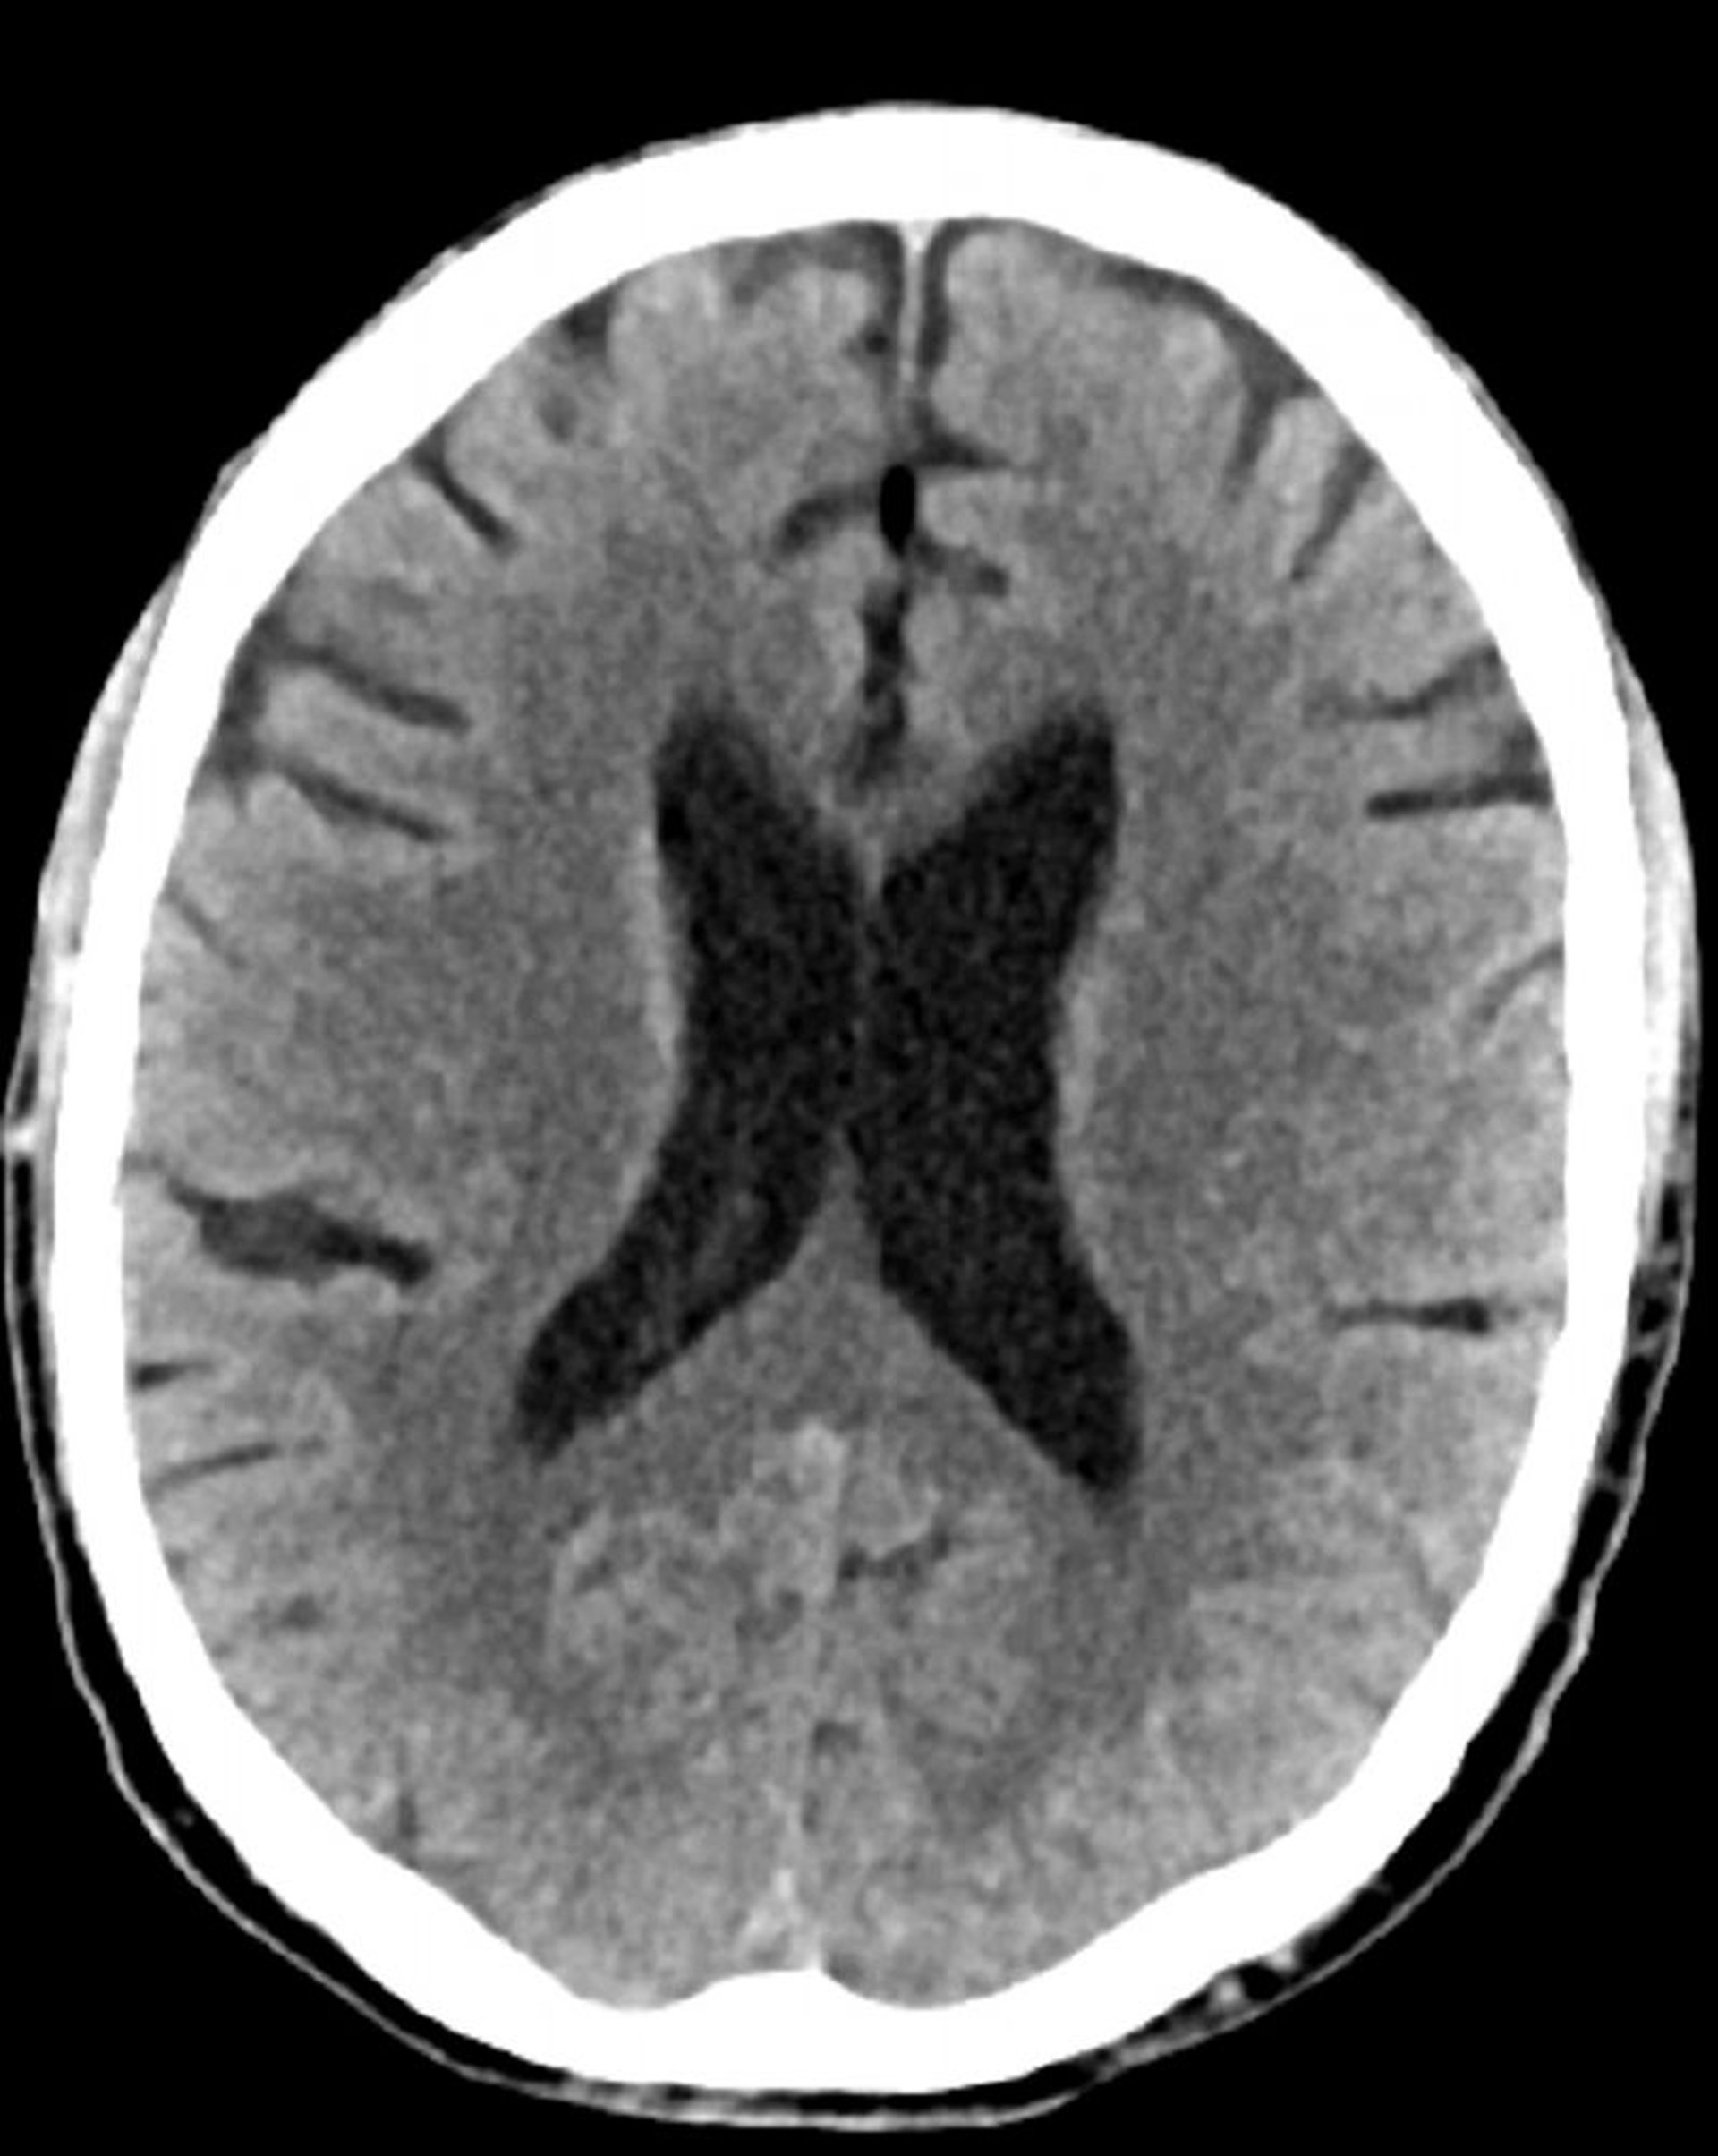

Tomografía computarizada craneal normal (adulto, 74 años)–diapositiva 4

Esta imagen es una tomografía computarizada craneal normal correspondiente a un adulto de 74 años. Cuando se compara con la tomografía computarizada craneal normal del adulto de 30 años de edad, se observa que los ventrículos y los sulcos son más grandes. Estos son hallazgos normales en este grupo de edad.